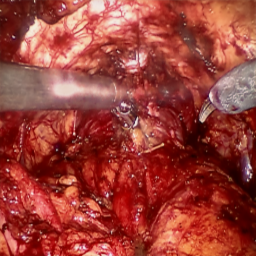

Refer to caption (a) Input Refer to caption (b) DIACMPN Refer to caption (c) Desmoke-LAP Refer to caption (d) PFAN Refer to caption (e) MITNET Refer to caption (f) Salazar Refer to caption (g) Dehamer Refer to caption (h) Ours Refer to caption (i) Target

Figure 3: Comparison of different methods on the LSD3K dataset.

IV-C2 Qualitative Analysis

Figures 3 and 2 provide a visual comparison of the desmoking results on challenging images from the test sets. The visual results corroborate our quantitative findings. DCP not only fails to remove the dense smoke but also introduces severe color distortion. CNN-based methods like FFA-Net and MSBDN successfully remove a large portion of the smoke but tend to either leave behind a thin layer of residual haze or over-smooth the image, losing critical textural details of the tissue and surgical instruments. The Transformer-based methods, DehazeFormer and PFAN, produce significantly better results by restoring more details. However, they can sometimes struggle with non-uniform smoke distribution, resulting in regions with unnatural brightness or minor artifacts.

In stark contrast, our RGA-Net generates visually superior results that are remarkably close to the ground-truth images. It effectively removes even the densest plumes of smoke while simultaneously preserving fine-grained details, such as blood vessels, tissue textures, and reflections on surgical tools. Furthermore, the color and illumination of the restored scene appear more natural and consistent, which is a direct benefit of our model’s ability to handle both local and global features through its hybrid attention and cross-gating mechanisms. This enhanced visual clarity is crucial for improving the surgeon-robot interface in real-world clinical applications.